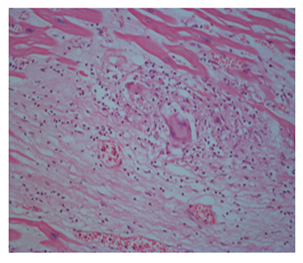

Our case was 34 years old male patient who had sudden loss of consciousness after discussing with another driver in traffic and he died on his way to hospital. The case brought to the Morgue Department of The Institute of Forensic Medicine of Adana, Turkey. Autopsy was performed and evaluated by two forensic medicine specialist and consulted to a pathologist. On internal examination, the heart weighed 340 g and thickness of left ventricular wall was 1,3cm, that of right ventricle was 0,1-0,3cm. Papillary muscles in both ventricles were fibrotic and showed disarrangement. Myocardial sections showed areas of fibrosis and dark-mottled areas. Microscopic examination of myocardial sections revealed connective tissue replacing normal myocardial muscle bundles; diffuse lymphohistiositic inflammatory cell infiltration, multinuclear giant cells (Figure 1). Microscopic sections of other internal organs showed no pathology other than hyperemia. On the basis of these findings, the final diagnosis was giant-cell myocarditis.

Figures 1 Myocardial lymphohistiositic inflammatory cell infiltration, multinuclear giant cells (HEX 100, HEX 200, HEX 400).